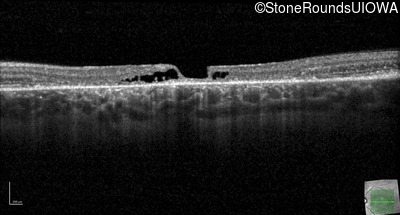

Optical Coherence Tomography - Left - 20/150

Exemplar / OCT Stack